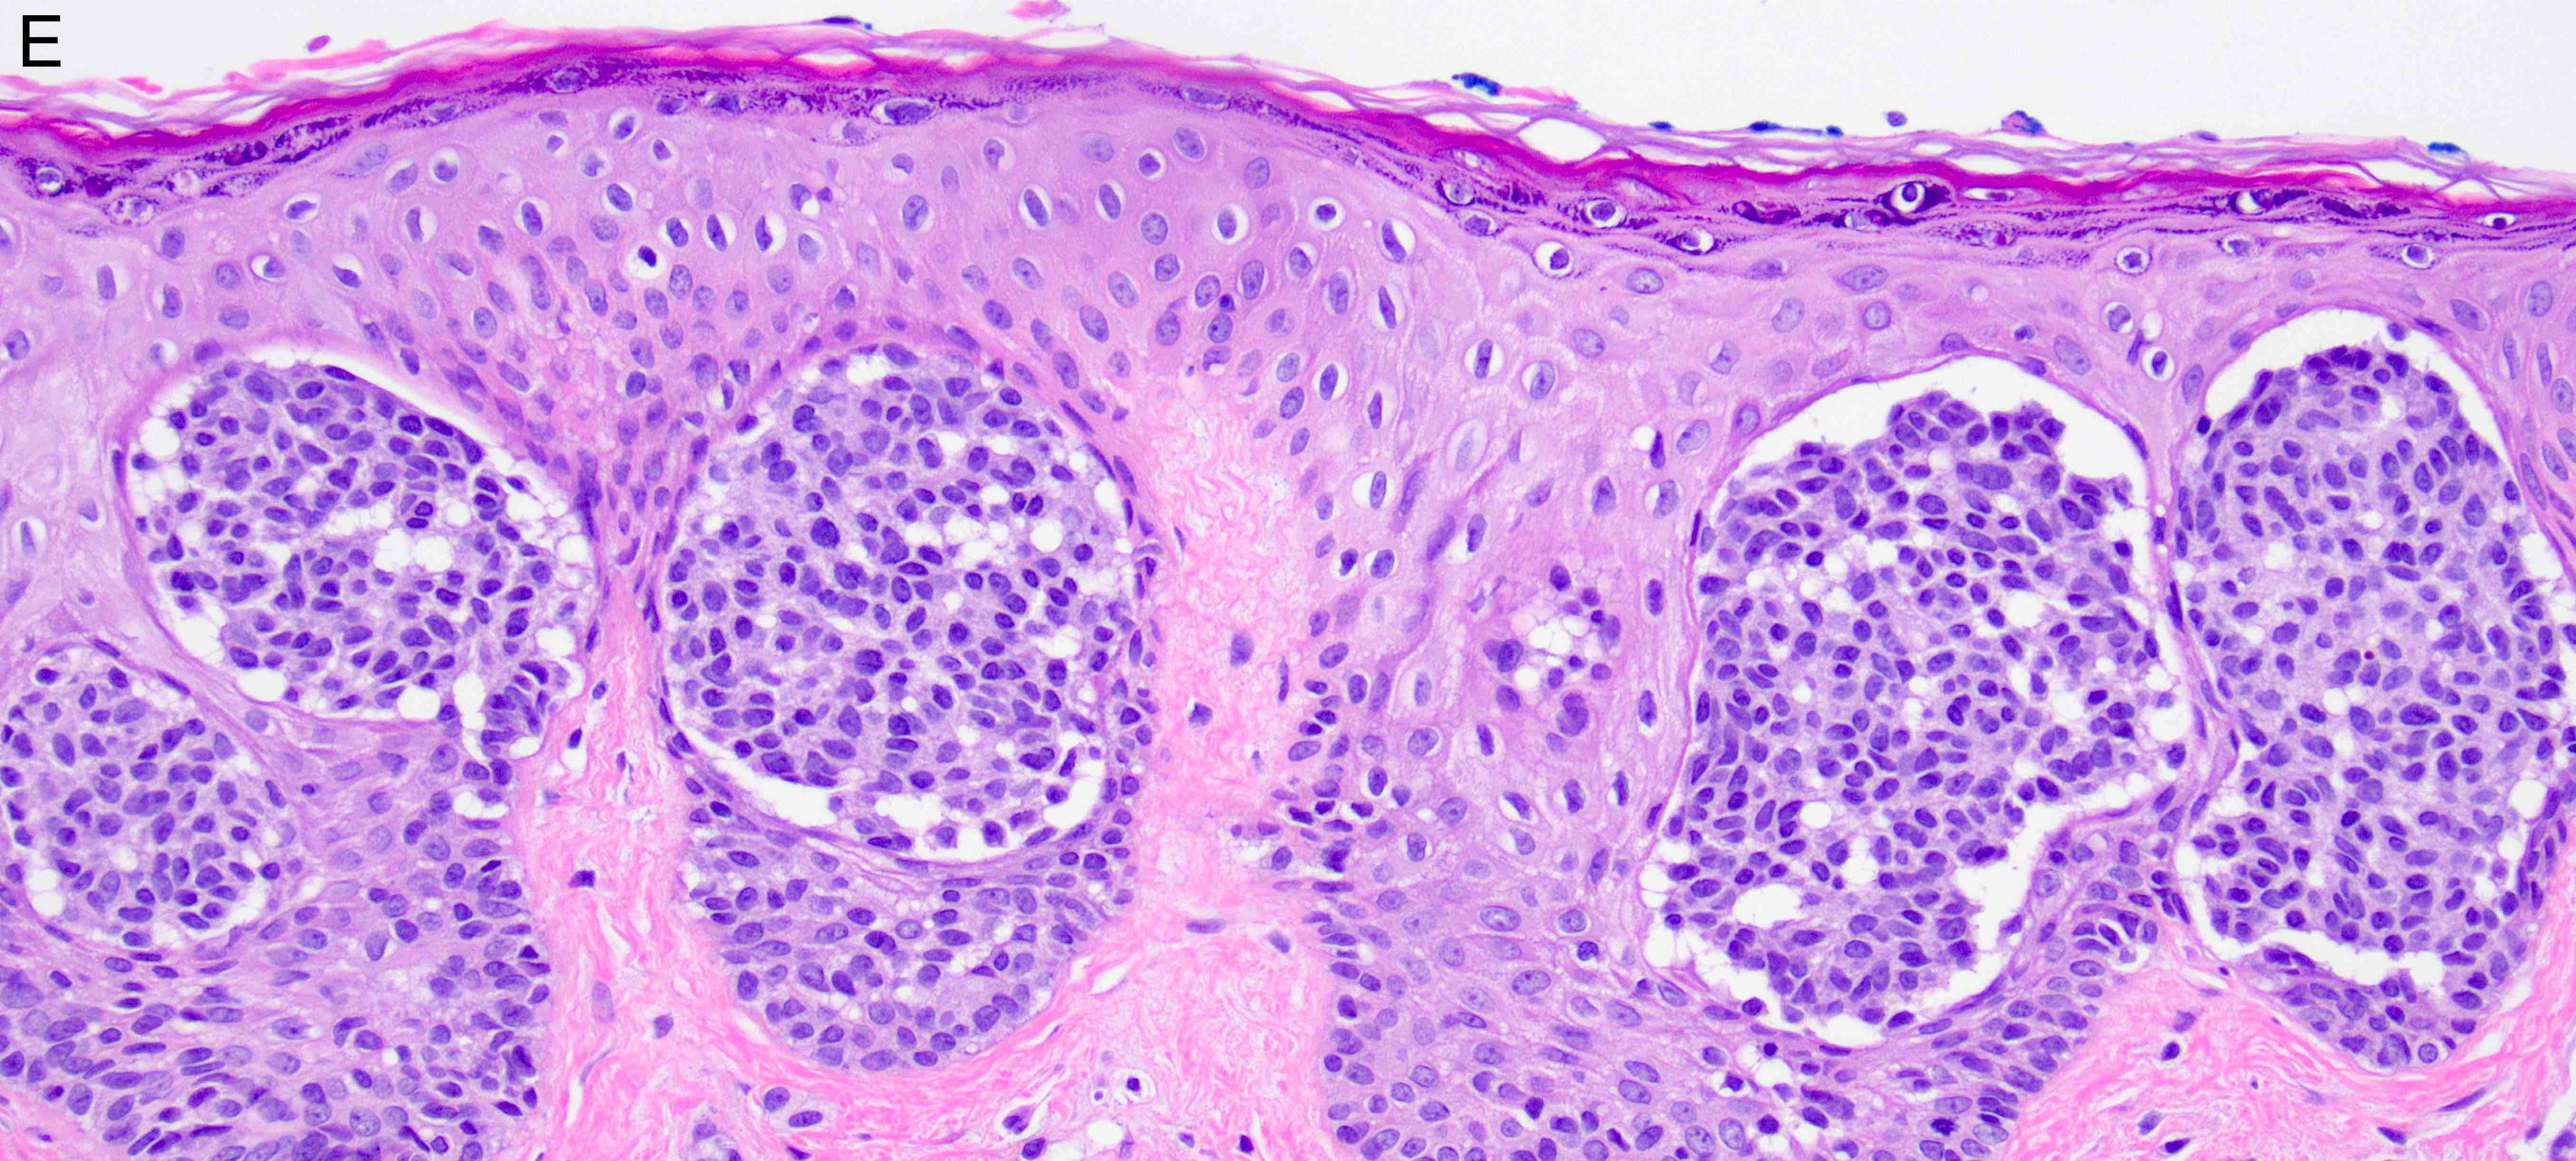

- Melanocytic nevi of the scalp (Am J Dermatopathol 2016;38:867):

- Melanocytes can be enlarged with irregular nuclei but atypia should be uniform throughout the nevus

- May contain large irregular nests in close proximity to one another

- Lentiginous growth may be prominent

- Pagetoid spread is a common feature

- Lesion can have broad junctional involvement and involve adnexa

- Single cell dispersion can be seen at lateral edges

- Lateral circumscription and maturation should be maintained, however symmetry may be lost (Am J Dermatopathol 2016;38:867)

- Prominent stromal fibrotic response can be seen

Microscopic (histologic) images